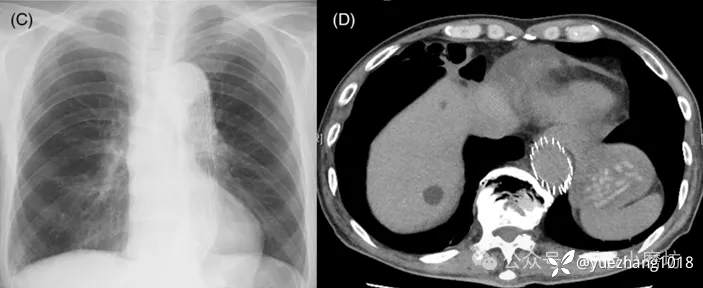

54岁女性患者,表现为突发胸膜炎样胸痛,初次发作后2天自行缓解。心电图和胸部X光都正常。3周后疼痛复发。

第二次就诊时胸片显示左心缘旁明确高密度影(图2A)。CT显示病灶为脂肪密度(CT值-48 HU),边缘见环状强化(图2B),并伴有邻近心包膜局限性增厚。

图2A 胸部X线片显示左心旁高密度影(箭头所示);2B 增强CT显示心旁高密度影对应被厚环包绕的心包外脂肪(箭头所示),注意伴随的心包增厚(箭)

予镇痛对症处理后患者疼痛于1周内消失。

2个月后影像学随访证实心旁密度消失(图2C)。胸部CT显示脂肪病变及邻近心包增厚显著减小(图2D)。

图2C 2个月获得的随访胸部X线片显示心旁高密度影已消失;2D 随访CT显示心包外病灶体积显著缩小(箭头所示),相邻心包增厚已消失